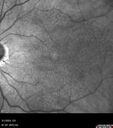

84 year old female The patient had cardiac stents done a week ago. Her stent was done late in the day. She did not notice anything that night but the next morning she noticed that it looked like there was steam coming out of the vent in the ceiling and like there was moister on the mirror. After that her vision changed to look like there was smoke inside her eye. This is more on the left eye than the right eye. Medical Hx: Influenza Immunization Not Received. Pneumococcal Vaccine Not Received. Diabetes Mellitus. Heart attack (2/23/2024). Hypertension, Systemic. Hyperlipidemia. Surgical Hx: Heart Stent (2/23/2024). Hysterectomy. Systemic Meds: Aspirin 81 mg. linaglitin. Metoprolol. NITROGLYCERIN. Ticagrelor. VALSARTAN. VA OD: Dcc20/32 Ncc20/200 VA OS: NccJ16 IOP: TP: OD:11 OS:10

reticular-drusen_119305_052424_06.jpg

Reticular pseudodrusen91 views00000